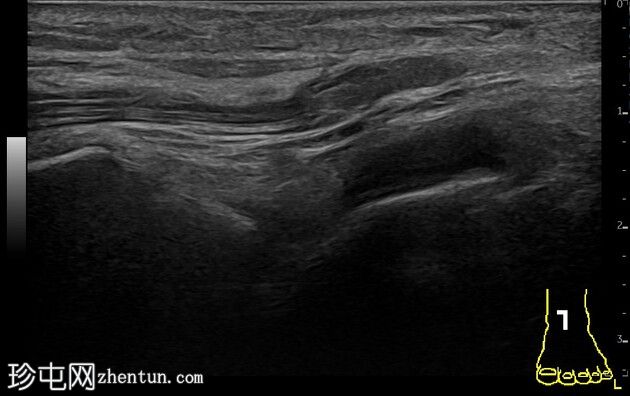

胫腓前下韧带撕脱伴腓骨骨骺损伤

踝关节前隐窝少量积液。患侧腓骨前下胫腓韧带撕脱。与对侧(右侧)相比,患侧韧带水肿。左侧腓骨远端骨骺增宽,邻近干骺端区域骨膜下少量出血。对侧(右侧)腓骨远端骨骺正常。距腓前韧带和跟腓韧带完整。跟骨前突未见撕脱。

本病例展示了超声在儿童踝关节损伤诊断中的应用价值。与健侧进行对比有助于诊断。